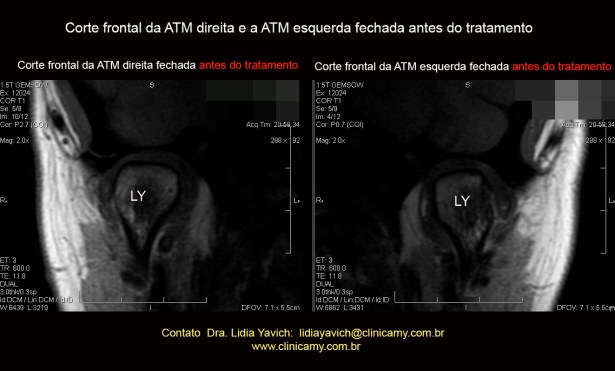

RNM: cortes frontais das articulações temporomandibulares direita e esquerda, boca fechada em oclusão habitual antes do tratamento.

RNM: cortes frontais das articulações temporomandibulares direita e esquerda, boca fechada em oclusão habitual antes do tratamento.

O corte frontal da articulação temporomandibular direita evidencia uma perda de espaço articular, especialmente na região do polo lateral externo da articulação. Ambas imagens frontais mostram diminuição do espaço articular.

Leve desvio discal medial.